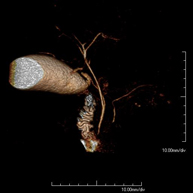

Prueba diagnóstica no invasiva que consiste en el estudio de la arteria aorta abdominal, obteniendo imágenes de alta definición anatómica mediante el empleo de un campo electromagnético y ondas de radio (con un emisor y un receptor). Es indispensable el uso de contraste paramagnético (Gadolinio). Sin embargo, no utiliza radiación ionizante. La calidad de las imágenes permite realizar reconstrucciones en 2D y 3D. Está indicado en aquellos pacientes con enfermedad vascular (aterosclerosis), estudio de aneurismas, en estudios pre-quirúrgicos de lesiones adyacentes a la aorta abdominal como "mapa" vascular, etc. - Angio RM Aorta-ilíaca

Prueba diagnóstica no invasiva que consiste en el estudio de la arteria aorta abdominal, obteniendo imágenes de alta definición anatómica mediante el empleo de un campo electromagnético y ondas de radio (con un emisor y un receptor). Es indispensable el uso de contraste intravenoso paramagnético (gadolinio). Sin embargo, no utiliza radiación ionizante. La calidad de las imágenes permite realizar reconstrucciones en 2D y 3D. Está indicado en aquellos pacientes con enfermedad vascular (aterosclerosis), estudio de aneurismas, en estudios pre-quirúrgicos de lesiones adyacentes a la aorta abdominal como "mapa" vascular… - Angio-RM Aorta iliaca